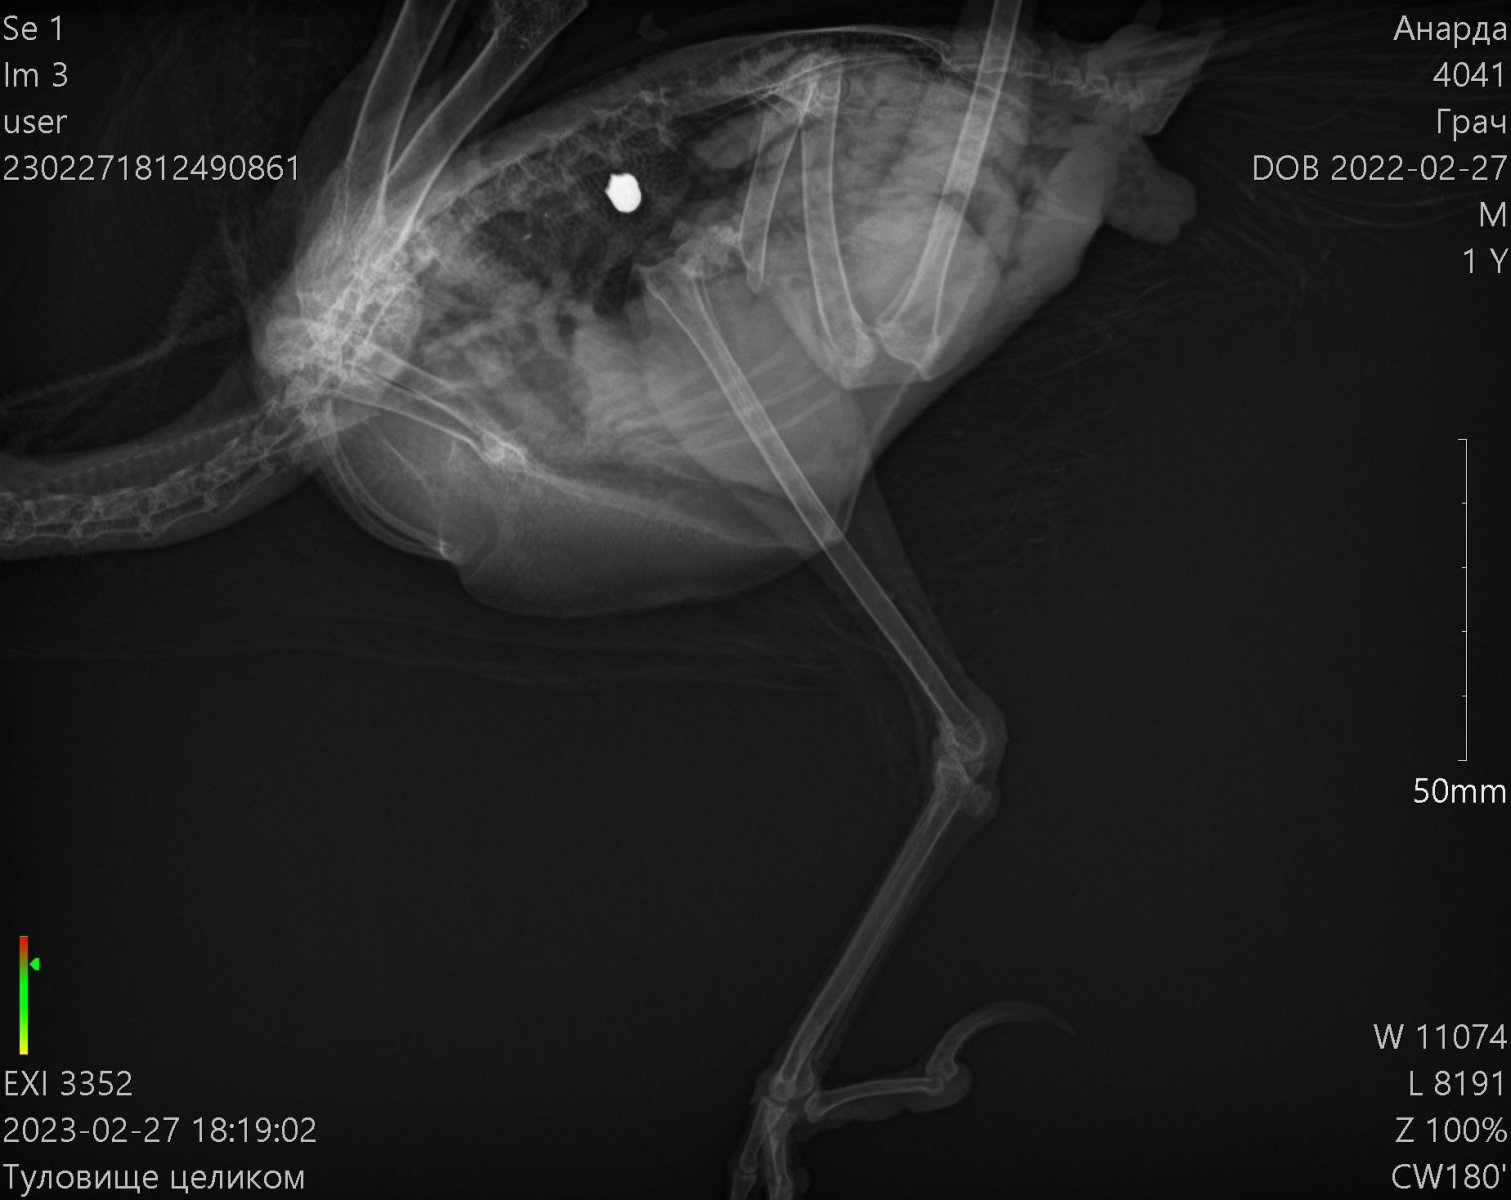

Доброго времени суток! Прошу строго меня не судить,так как оказался заложником ситуации ведь в отношении таких птиц не имел опыта совсем. Напишу вкратце. Шёл вечером домой,вижу лежит грач живой,ну я не смог пройти мимо и забрал его с собой.Повез к ветеринару,тот его пощупал и сказал что он травмирован и ничем помочь не может, сказал пусть поживёт у тебя месяц два, отойдёт и если все хорошо оклимется и улетит... Через месяц ничего не произошло, грач как хромал так и хромает, взлететь пытался но не смог. За это время я ему сделал вольер большой 2 метра в высоту и 5 в длину, научился правильно кормить. В общем понял что нарвался я на горе ветеринара и повёз в дорогую клинику, где сделали качественные снимки, оказалось его подстрелили, снимки прикреплю в тему. Сделали анализы, прописали лекарства, от паразитов, клещей итд. Но самое неприятное это то, что сказали что он летать не будет и ему нужна операция, каких у нас в Пятигорске нельзя осуществить. Подскажите пожалуйста, как нам быть? Кто сможет помочь нам? У нас в крае травили грызунов, средством которое запретили 35 лет назад, в итоге весь наш город и край усыпан трупами грачей, прямо везде даже в центре города,а своего я вроде думал что спас, но как оказалось нет :(